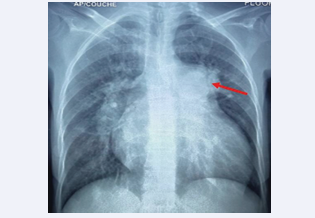

There was also grade III pulmonary insufficiency with severe pulmonary hypertension (80 mmHg). Abdomino- pelvic angioscan revealed a patch of intra-parenchymal splenic hypodensity suggestive of an upper mid-polar splenic infarction measuring 39x33x36 (Figure 3); the other viscera were normal. Biological tests were normal.

Figure 3 Axial-section injected abdomino-pelvic angioscan showing an upper mid-polar splenic infarct measuring 39x33x36 (star).

Figure 3:  Axial-section injected abdomino-pelvic angioscan showing an upper mid-polar splenic infarct measuring 39x33x36 (star).